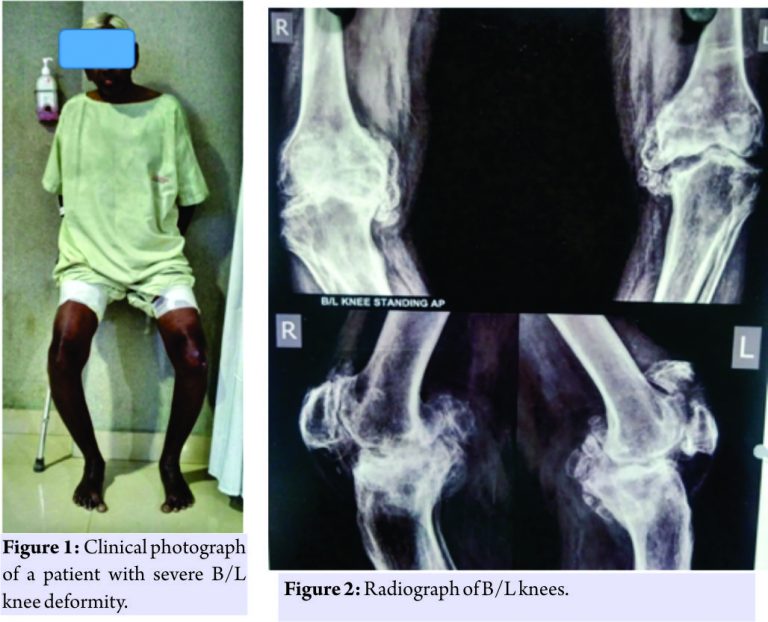

The patient was having pain, swelling, but he had not taken any treatment for it. Patient neglected the injury and was able to walk with the support of walking aid. On examination, the patient was having bilateral knee Varus 20°9 (Fig. 1) and fixed flexion deformity of 30°. Active straight leg raising was not possible on the left side. Range of movement of left knee was possible from 30 to 90°. Radiographs revealed a transverse fracture of the patella with Grade 4 osteoarthritic changes on the left side and arthritic changes on right knee also (Fig. 2).